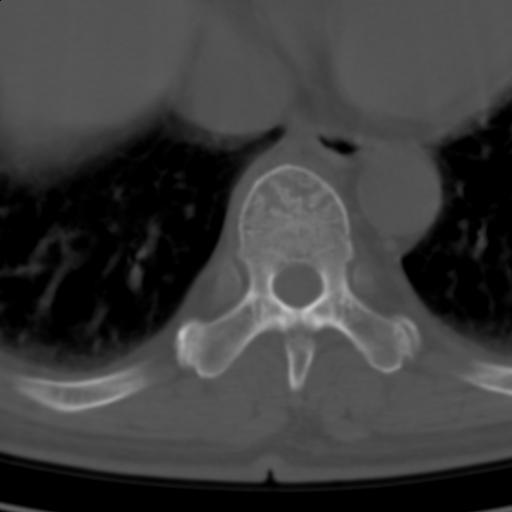

标题: CT25189:胸椎ct,请会诊!

既往食管癌,现行ct检查!

仅见椎体退行性改变

中上段食道癌,椎体轻度退变。

椎体退行性改变,食管癌。

支持中上段食道癌,椎体轻度退变,必要时做ect。

支持中上段食道癌,椎体轻度退变。